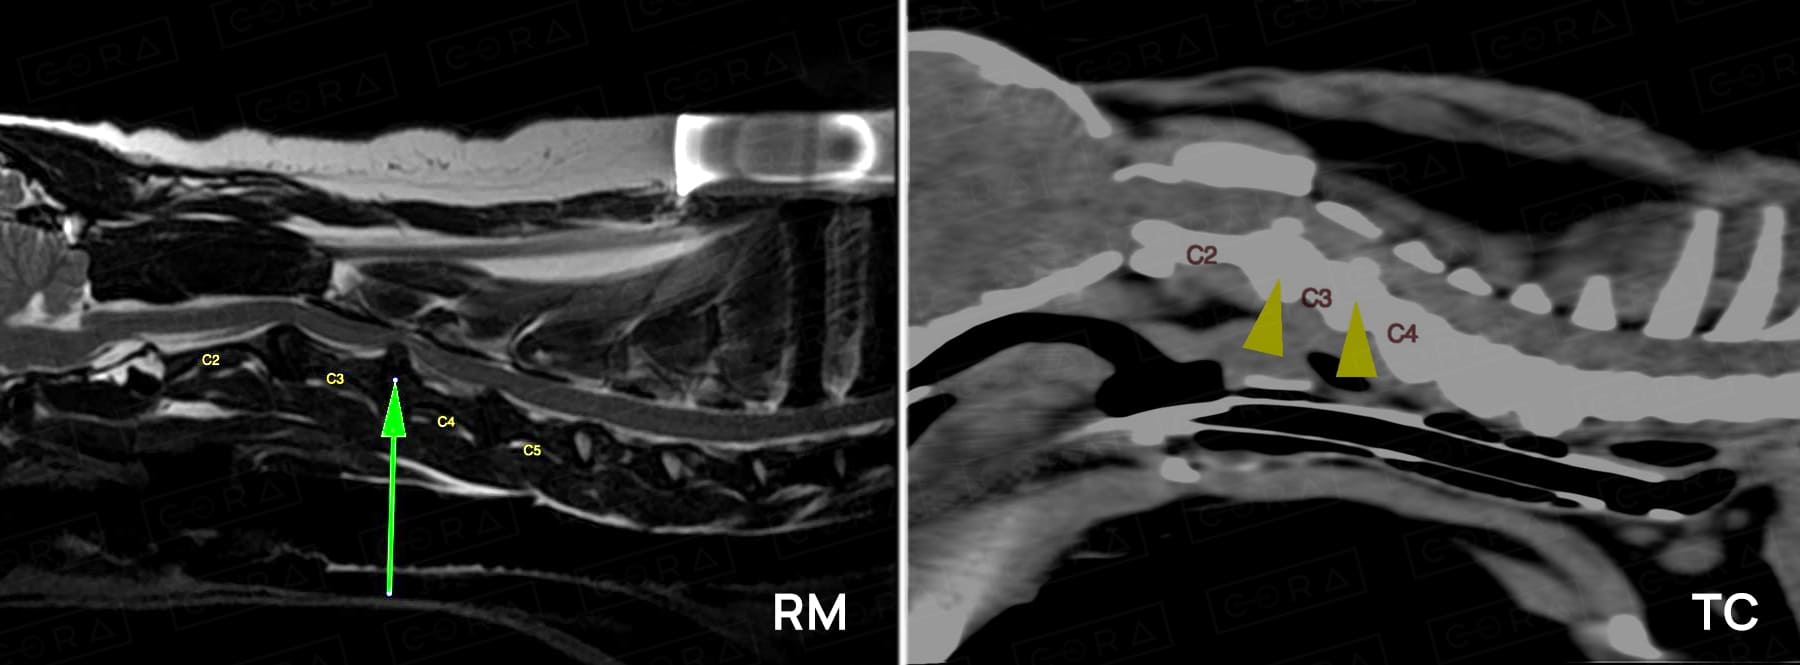

O diagnóstico é realizado por meio de exame físico e neurológico, e deve ser complementado com exames específicos de imagem, como a tomografia 3 e ressonância magnética.

Em contrapartida, esses animais sofrem com dor crônica e podem ter uma recuperação mais lenta após o tratamento. Entretanto, em ambas as condições, o tratamento visa a descompressão pela técnica que o cirurgião achar mais pertinente para o caso clínico, de acordo com o exame neurológico e as imagens obtidas pela tomografia ou ressonância magnética (slot ventral, corpectomia, hemilaminectomia 5 , laminectomia ou pediculectomia).